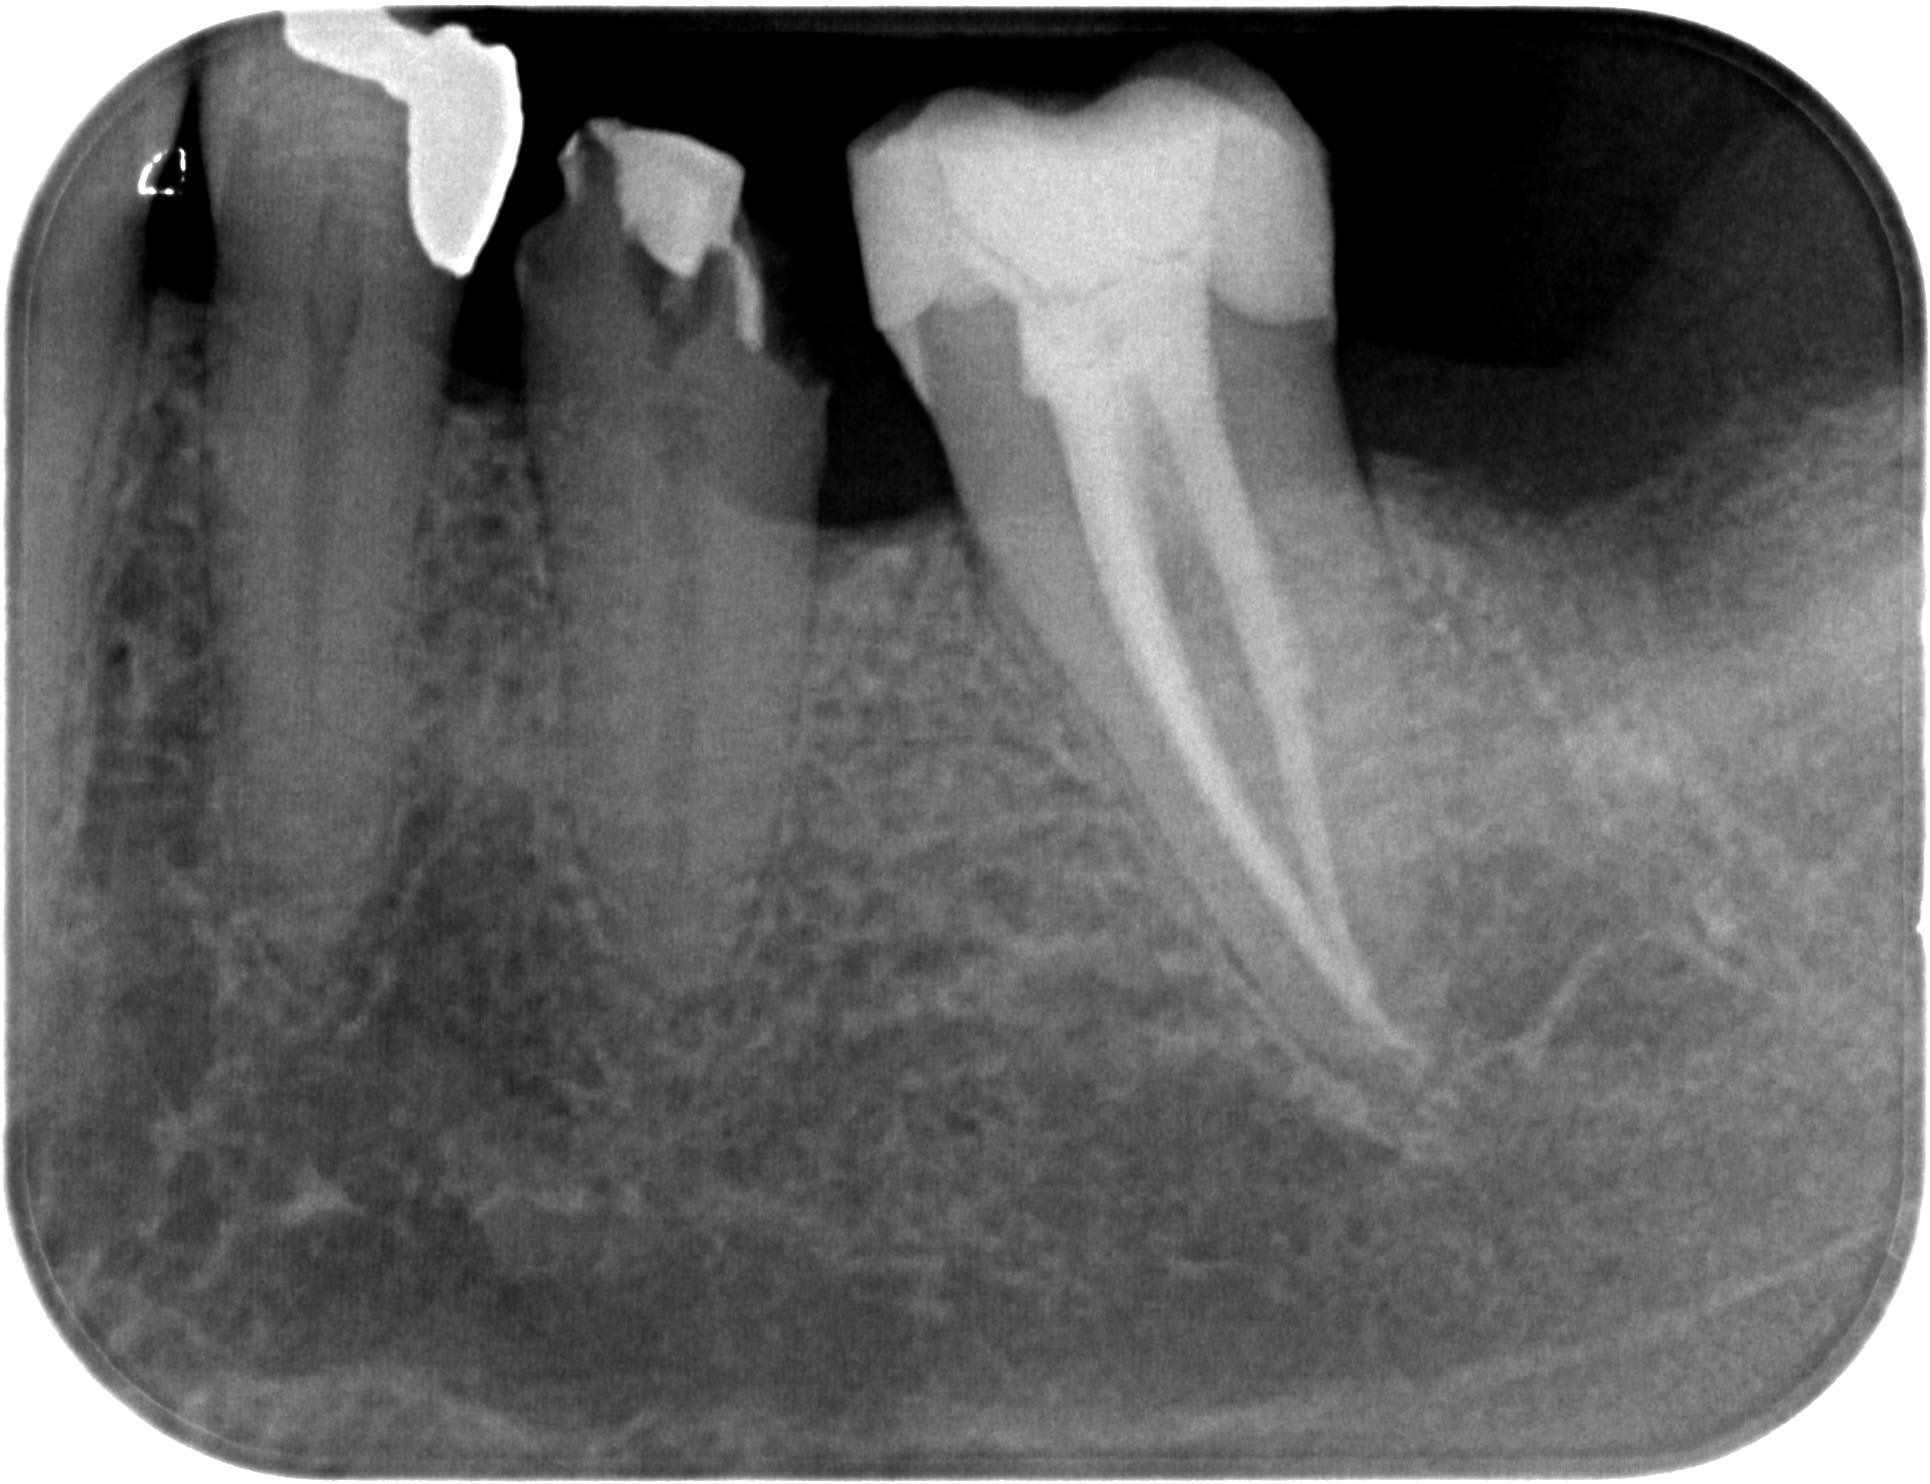

SP24 (2 von 5) Veröffentlicht 4. Juli 2016 am 1930 × 1484 in Dentikel als Ursache von Zahnschmerzen ?